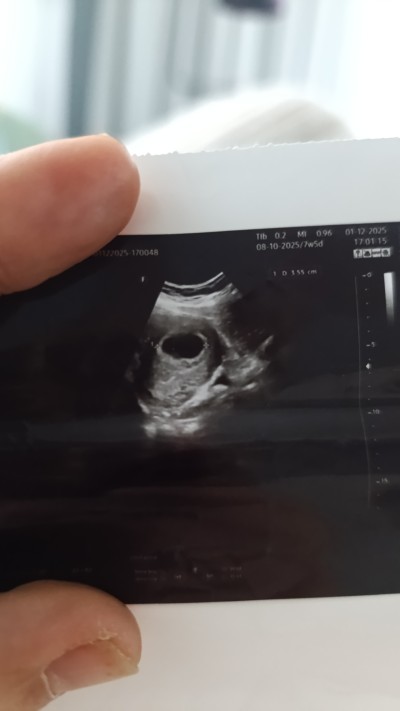

7 haftalik hamileyim. Ama ultrosonda kalp atışları duyulmuyor. Normal mi?

Gebelik haftası 7 hafta

Merhaba, cevabınız için teşekkür ederim. Kesemi gördü doktor fakat içinde bebek yok, kalp atışı mevcut değil die kürtaj yapmak istediğini söyledi. O yüzden yazma gereği duydum. Sizce beklemeli miyim? Hatta buda ultrason kagidimiz .

image

Kese şuan büyük ve bebek oluşması gerekiyordu dedi 2-3 doktora ve özel hastaneye gitmiş olmama rağmen . Ve kürtaj denildi. Ama doktorun birisi de kesenin içerisinde organa benzeyen bir şey var bu canlanadabilir canlanmayadabilir dedi. Yani inanın ne yapacağımızı şaşırdık. Kendi doktoruma daha randevuma var. Cuma günü için gelmemi söyledi. İlk gittigimde çok küçük olduğunu keseyi gördüğünü fakat içerisinde ufak bir parça gördüğünü de eklemişti. Ama ben 4 gün ufak bir kanama yüzünden hastanede yattım. Bugünde kesenin var olduğunu fakat kalp atışı olmadığını bebeğin oluşmadığını ve kürtaj olmamı söylediler. Çevremdeki insanlar da çok normal diyor. 9-10 haftaya kadar bekle deniliyor

Biraz daha bekle derim en azından 8. Haftaya kadar ama kese oluşmuş içi boş ise yapacak birşey yok doktorlar ne derse doğrudur ama şimdiye kadar 14 mm olması gerekirdi kalp atışı olmalıydı dk 150 kez hatta belki geç döllenmiş olabilir bekle bakalım